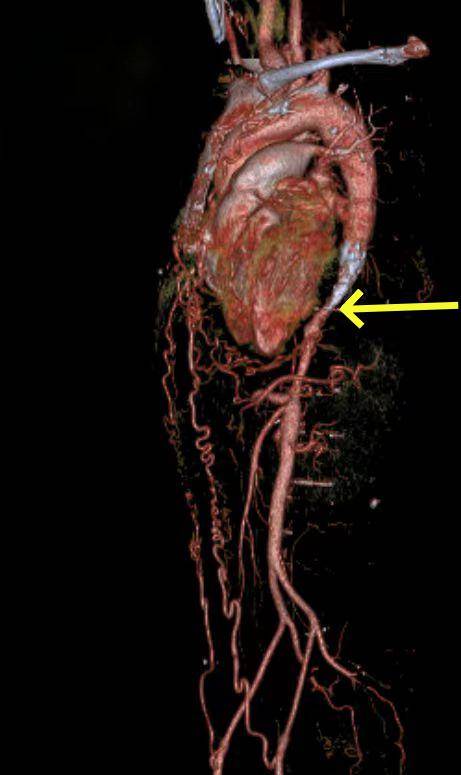

包块原来是"巨大腹主动脉瘤,双侧髂动脉瘤,瘤体近端远端扭曲钙化严重"

这个炸弹好危险 巨大腹主动脉瘤手术

不太大但超级难的腹主动脉瘤

男子腰腹部疼痛,原来是长了复杂性罕见巨大腹主动脉瘤